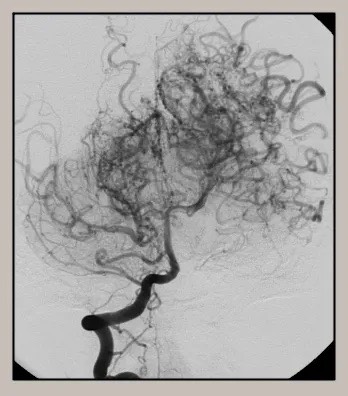

모야모야병은 뇌혈관, 특히 뇌로 혈액을 공급하는 내경동맥과 그 주변 주요 혈관이 점점 좁아지고 막히는 희귀 난치성 질환으로, 혈류가 줄어든 뇌는 부족한 혈액을 보충하기 위해 가느다란 미세측부혈관들을 새로 만들어냅니다. 이 작은 혈관들이 연기처럼 보인다고 하여 일본어로 ‘모야모야(안개·연기)’라는 이름이 붙었습니다. 소아부터 성인까지 폭넓게 나타나며, 특히 5~10세 어린이와 30대 전후의 여성에서 비교적 많이 발견되는 경향이 있습니다. 증상은 일시적 마비, 언어장애, 두통, 실신, 경련 등 매우 다양해 뇌졸중과 유사하거나 초기에는 가벼운 신경학적 증상으로만 나타나 진단이 늦어지기도 했습니다. 질환이 진행하면 허혈성 뇌졸중(뇌경색)이나 출혈성 뇌졸중 위험이 증가하여 반드시 전문적인 관리가 필요합니다. 아직 완전히 예방할 수 있는 방법은 없지만 조기 진단과 적절한 치료를 통해 뇌 기능을 보호하고 삶의 질을 유지할 수 있습니다.

모야모야병은 뇌기저부의 주요 혈관이 서서히 협착되고 막히면서 뇌혈류가 감소하는 만성 진행성 뇌혈관 질환입니다. 협착이 진행된 부위를 대신해 뇌는 생존을 위해 얇고 약한 혈관망을 만들어 혈류를 보충하려 하고, 이 새로운 혈관들이 촬영 영상에서 연기처럼 퍼져 보인다고 하여 ‘모야모야’라는 이름이 붙었습니다. 기전적으로는 내경동맥 말단부와 중대뇌동맥·전대뇌동맥의 기시부에 병변이 가장 잘 생기며, 시간이 지남에 따라 양쪽에 대칭적으로 나타나는 특징을 보였습니다. 이 질환은 단순한 혈관 협착이 아니라 진행성 변화이기 때문에 치료하지 않으면 혈류 부족이 심해지고 뇌 손상이 누적될 수 있습니다. 또한 뇌기능이 체력·호흡·체온 변화 등에 민감하게 반응하기 때문에 과호흡, 울음, 격렬한 운동, 감염 등으로 증상이 악화될 수 있습니다. 즉, 모야모야병은 시간이 지나면서 뇌혈류를 감소시키고 뇌졸중 위험을 높이는 질환이며, 평생 관리가 필요한 만성적 특성을 갖고 있습니다.